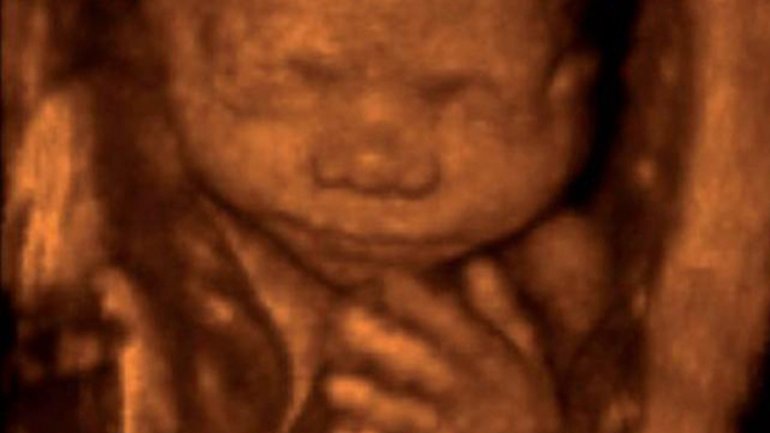

Ultraschall 17. SSW

Auf dem 3-D-Ultraschall erkennt man schon deutlich das kleine Gesicht des Fötus, der jetzt ungefähr 10,6 Zentimeter vom Scheitel bis zum Steiß (SSL) misst. Unter dem Kopf sind auch die Hände gut zu sehen. Links am Kopf entlang und dann über die Brust des Babys verläuft von oben nach unten die in sich gedrehte Nabelschnur.